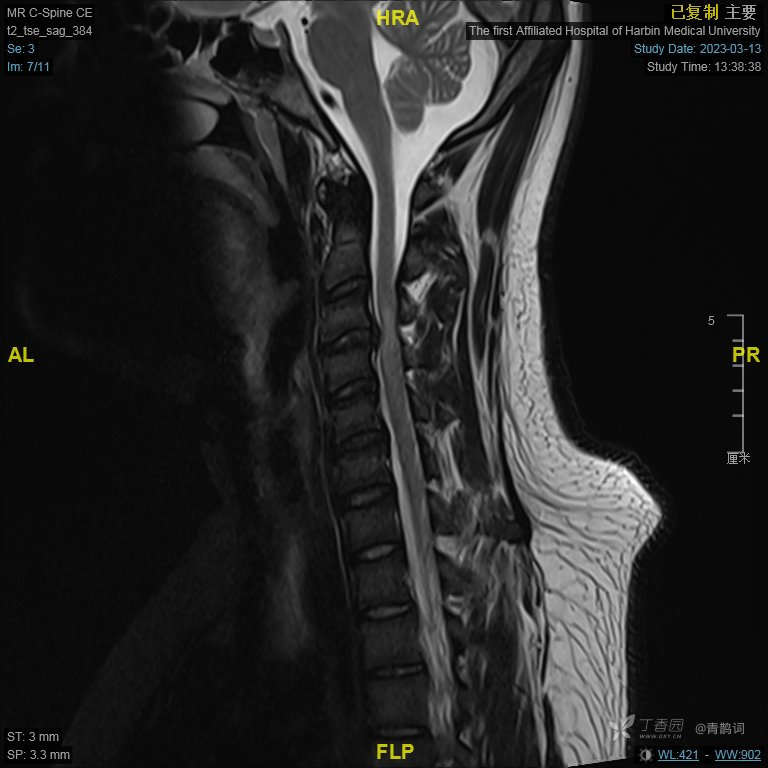

颈部磁共振平扫后增强: